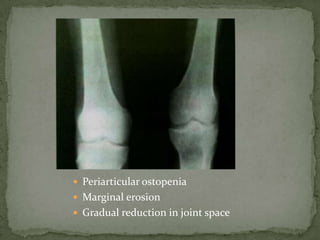

 Periarticular ostopenia

 Marginal erosion

 Gradual reduction in joint space

 Periarticular

osteopenia

 Erosions

 Symmetric reduction

of joint space